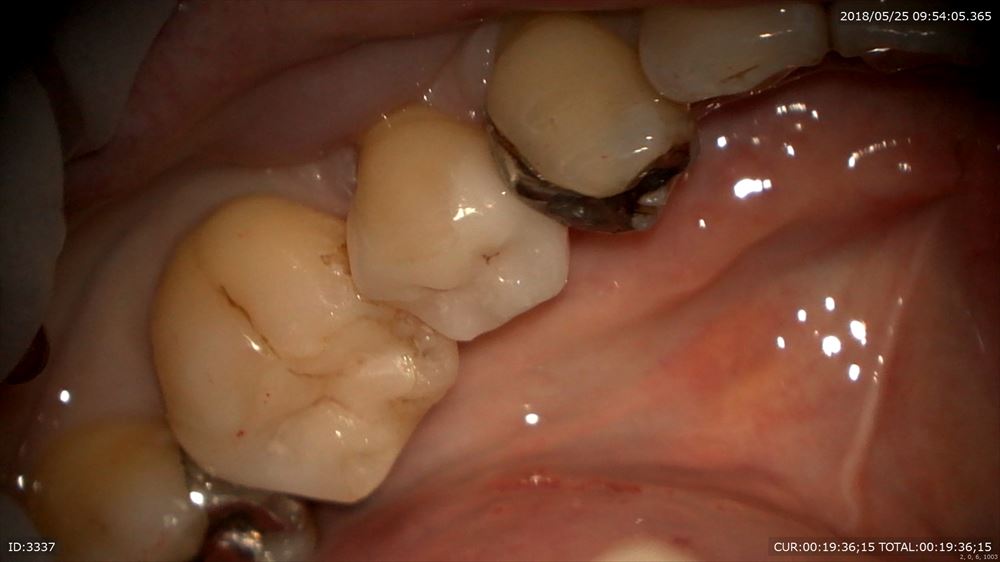

セット

違和感も消えました。

歯茎の下までの虫歯も精密治療でこの様に2回で治ります。